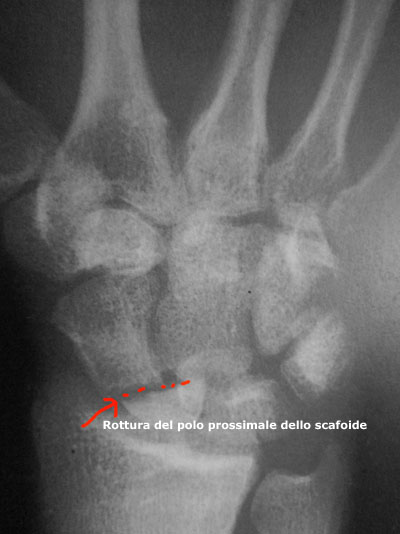

Diagnostica per immagini.

Le radiografie convenzionali rimangono la pietra angolare dell'immagine iniziale è del seguito. Si compiono i radiogrammi in proiezione postero-anteriore, laterale, in deviazione ulnare (proiezione dello scafoide) e obliqua. Queste proiezioni sono valutate per ricercare una pseudoartrosi, una scomposizione, un’instabilità e alterazioni degenerative. Per la valutazione della guarigione dello scafoide, i radiogrammi convenzionali possono essere inadeguati. Si deve fare attenzione a non scambiare una sovrapposizione dei frammenti per una guarigione. Se vi sono dei dubbi sulla guarigione, si raccomanda di eseguire per monogrammi o scansioni TC. La termografia (stratigrafia) effettuata in cinque piani con tagli di 2 mm, una scansione con tagli di 1-1,5 mm nell'asse longitudinale dello scafoide serve allo stesso scopo. Entrambe le tecniche permettono un’accurata valutazione della guarigione, della scomposizione e delle alterazioni degenerative. Se si pianifica un trapianto osseo di una pseudoartrosi, ma si sospetta una necrosi avascolare, si effettua una scansione di risonanza magnetica. Una necrosi avascolare dello scafoide, in particolare del polso prossimale, è importante fattore predittivo della riuscita della chirurgia per correggere la pseudoartrosi dello scafoide. Sebbene sia noto che i radiogrammi convenzionali non dimostrano accuratamente una vera necrosi avascolare, è stato dimostrato che una diminuzione dell'intensità del midollo osseo nelle immagini T1-pressate dalla risonanza magnetica ha un’alta specificità per la necrosi avascolare.